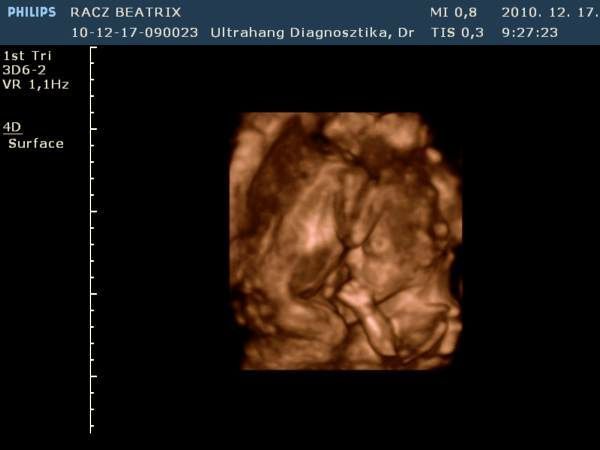

Gyorsan növöget az egyszemkénk, remélem lassan megtudjuk a nemét is! Afp-re dec. 27-én megyek. Az "A" baba még mindig ott van a hegemen és már úgy néz ki ott is marad, majd elnyomja a "B" baba mikor már nagyobb lesz kb a 18-20. héten. De van olyan is akinek szülést követően a méhlepényén találják meg mint egy freskót rajta. Teljesen ott lesz a lenyomata. Majd meglátjuk mi lesz...